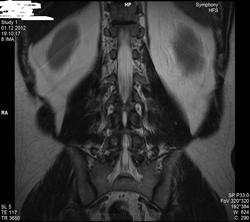

Уважаемые специалисты. МРТ после операции 8 нед.

Операция геминоламинэктомия L4-5 с установкой системы динамической стабилизации между остистыми 4-5.

После операции боли в пояснице прошли, боль в коленях и голенях осталась в неизменном виде. Ниже верхней трети голени боль не опускается.

По задней стороне туловища в ногах болей никогда не было. Уважаемый специалист, к сожалению не рентгенолог, утверждает что нет никаких признаков радикулопатии. Не посмотрите своим профессиональным взглядом.